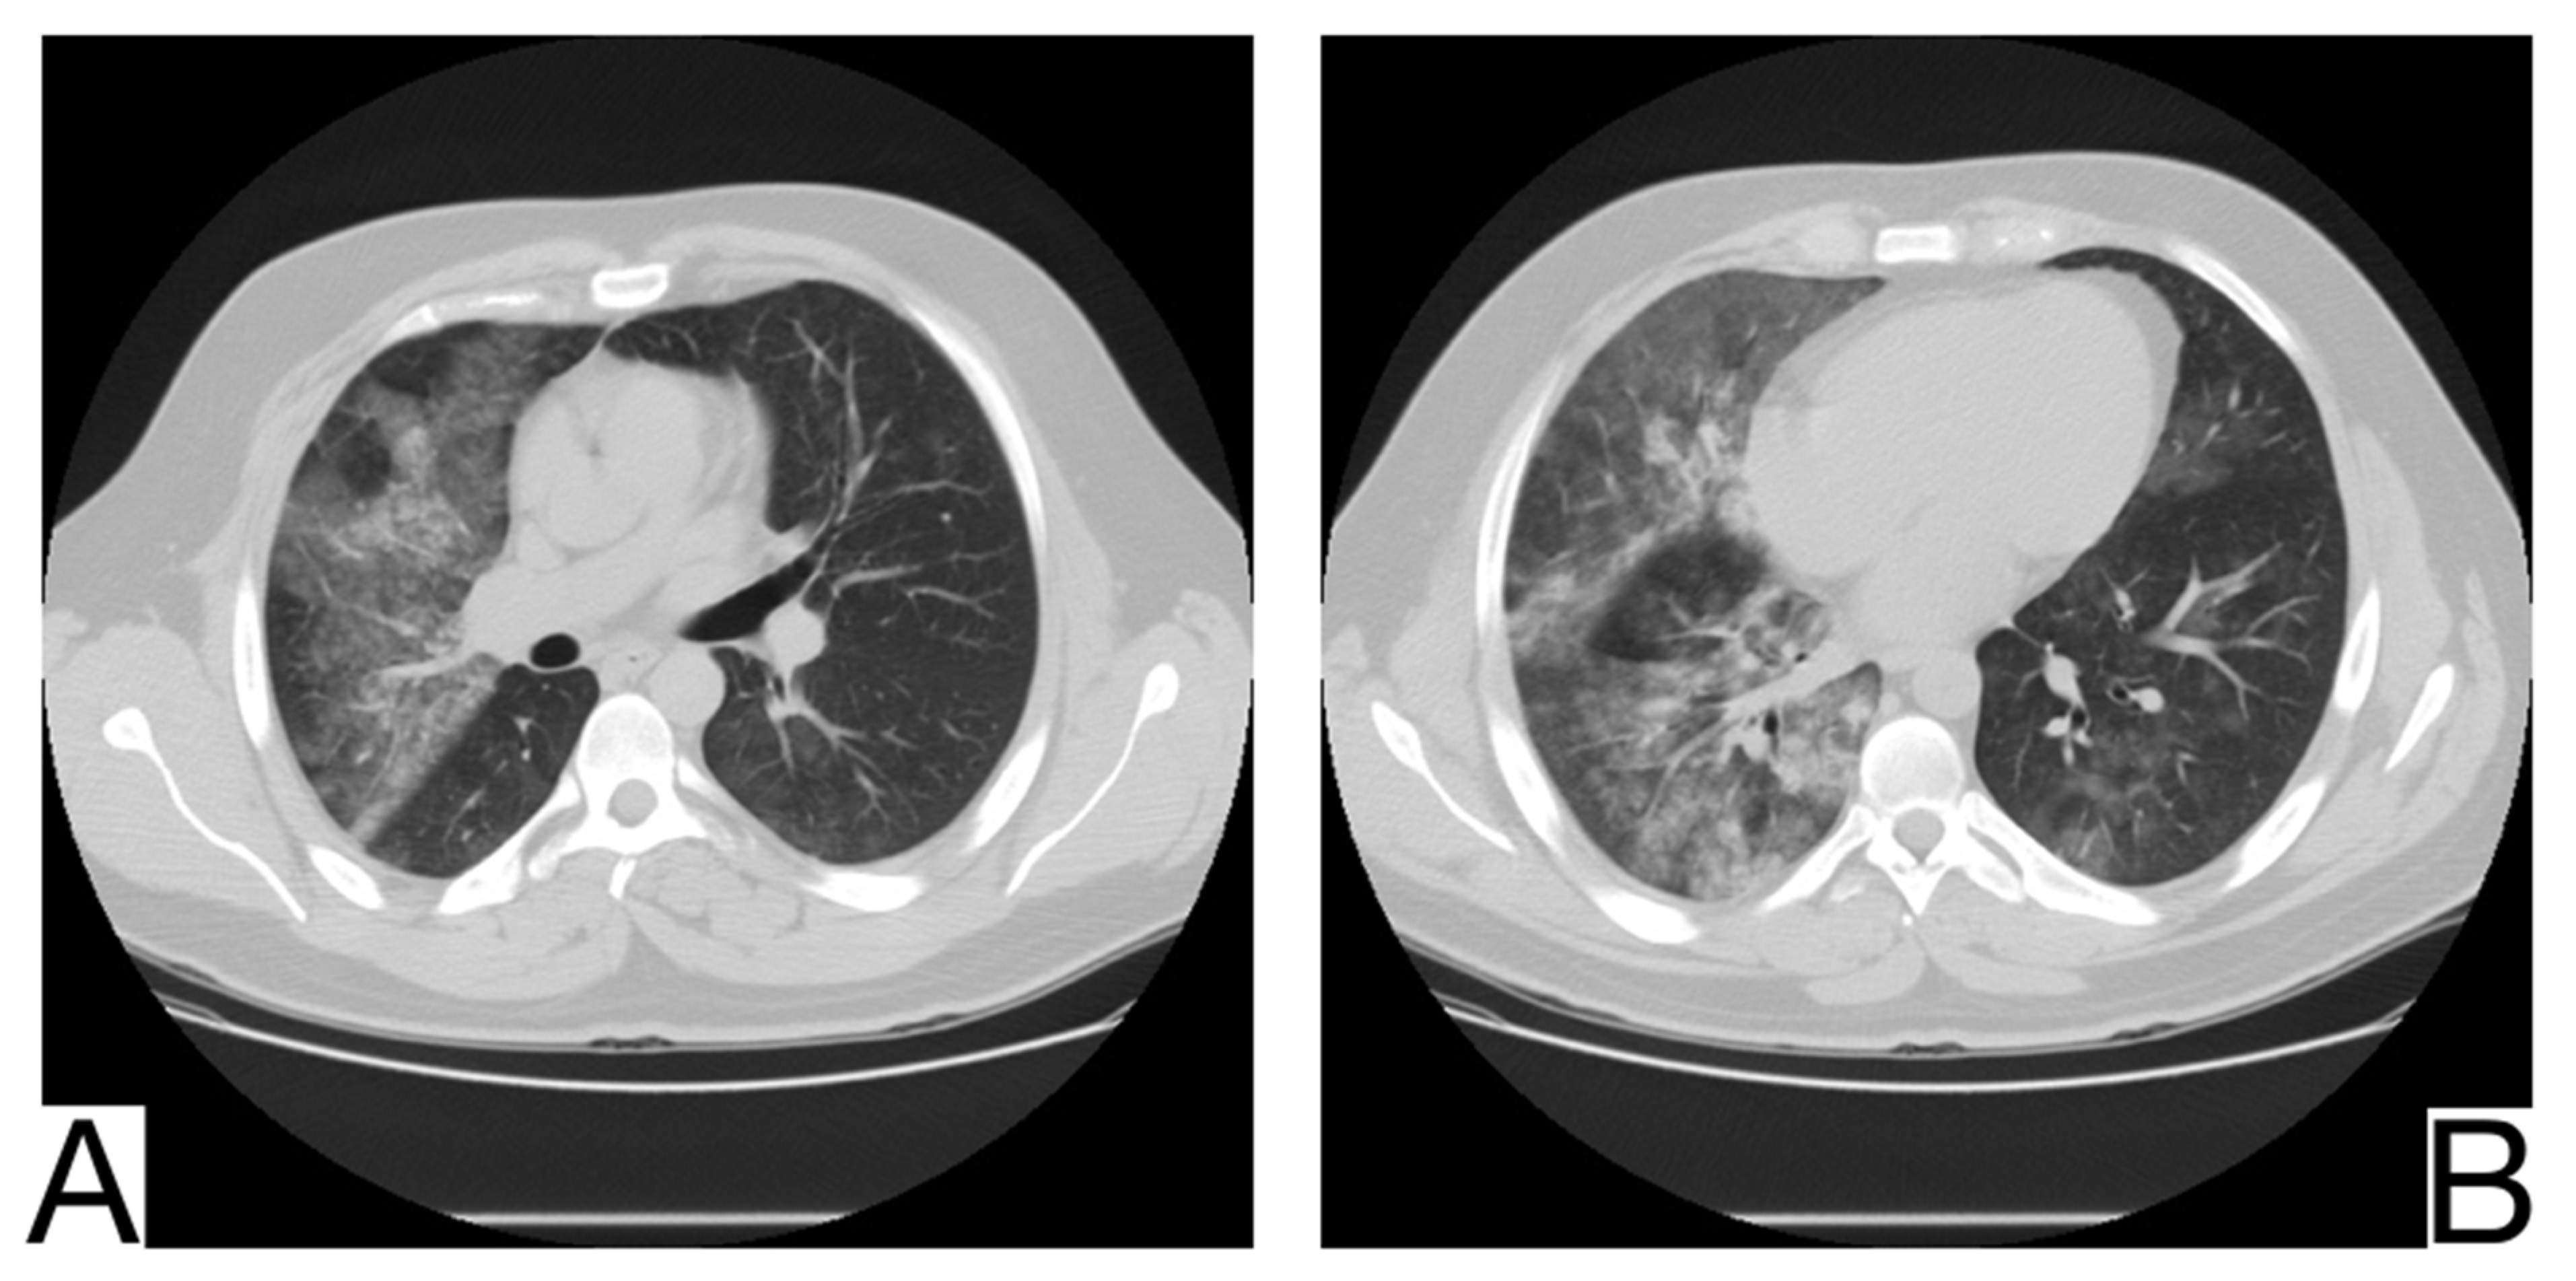

10.8. Eosinophilic Pneumonia

10.9. Aspiration Pneumonia